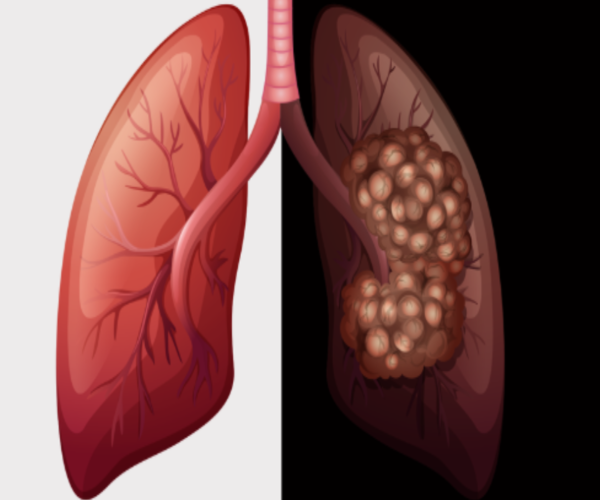

암이란 몸속의 정상적인 세포들이 돌연변이를 유발하면서 발생한 이상세포들을 말해요. 암이 생겨나게되면 다른 장기로 전이되며 증식을 자꾸 일어나서 장기의 기능을 훼손을 의미해요.

폐암은 암 사망률 1위이면서, 발생도 4위일 정도로 병이 나서율이 높은 암이면서 조기 발견이 어렵습니다. 폐암은 소세포암과 비소세포암으로 나뉘는데 소세포암은 전이가빠르고 악성 정도가 높아 무서운 암이라고 할 수 있습니다.

비소세포암은 폐암 전체의 약 70% 입수할리만큼 대개 비소세포암이 생겨나게 돼요. 비소세포암은 편평상피암, 선암, 대세포암으로 나누어져요.

폐암가운데 15~20%는 소세포폐암으로 악성도가 높은 암이희망하더라고요. 소세포암은 발견 당시 이미 림프관, 혈관을 통해 다른장기나 반대편폐, 종격, 심장, 기관, 식도, 대동맥 등으로 전이되는 경우가 많으므로서 치료 후 경과가 굉장히 좋지않은 암이에요.